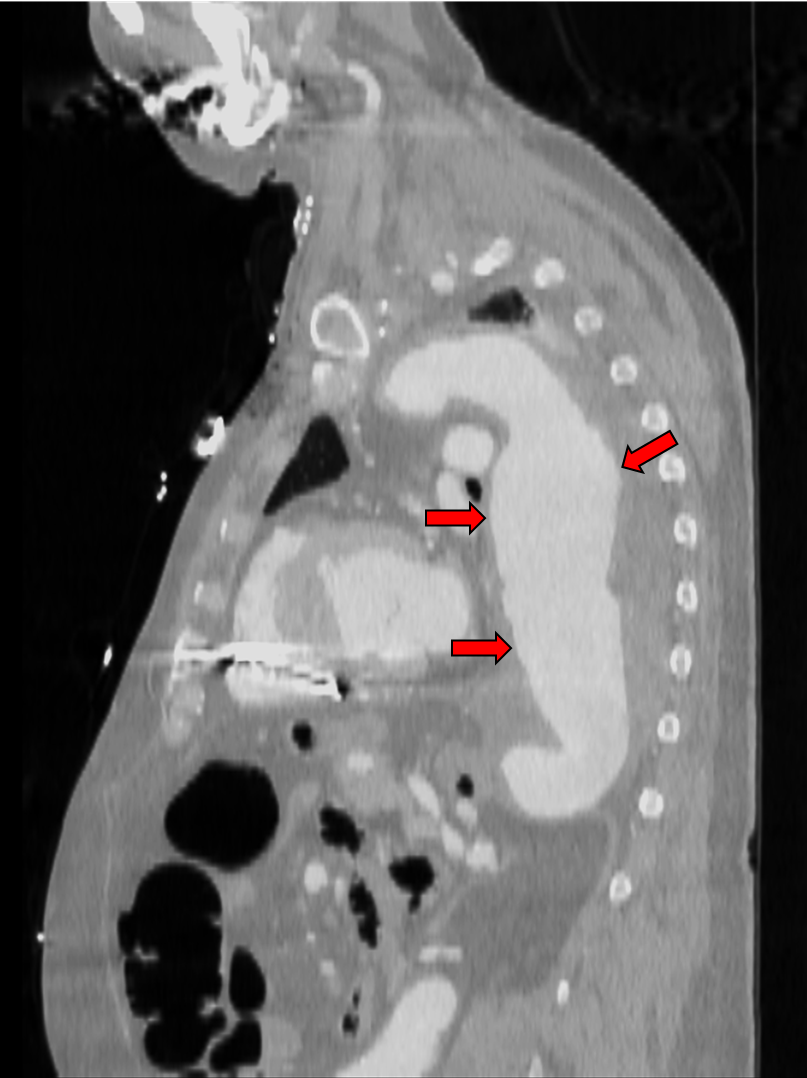

Im Zuge des Alterns oder aufgrund von Herz-Kreislauf-Erkrankungen (Arteriosklerose, Bluthochdruck), der genetischen Veranlagung oder durch Rauchen können sich Abschnitte an Arterien krankhaft aufweiten. Bei einer krankhaften Erweiterung der Hauptschlagader (Aorta) oberhalb des Zwerchfells (Brustaorta) auf einen Durchmesser von mehr als 50 % des Normwerts spricht man von einem Aortenaneurysma, das spindel- oder sackförmig aussehen kann und gefährlich ist. Unbehandelt können sich aus Aneurysmen an der Aorta die höchst gefürchteten Dissektionen („das Gefäß platzt“) entwickeln – auch heute ein Notfall, der häufig tödlich endet. „Weil das erkrankte Gefäß ab einem bestimmten Durchmesser oder beim Auftreten von Beschwerden mit einer Prothese versorgt werden muss, sind auf diesem Gebiet Neuentwicklungen, die der Sicherheit und der Verbesserung der Lebensqualität der Betroffenen dienen, besonders wichtig“, betont Prof. Dr. med. Hellmut Oelert, Vorsitzender des Wissenschaftlichen Beirats der Deutschen Stiftung für Herzforschung (DSHF) – von der Deutschen Herzstiftung 1988 gegründet (www.herzstiftung.de). Während der Eingriff früher nur mit Hilfe einer offenen Operation möglich war, lässt sich heute die Prothese in immer mehr Fällen katheterbasiert (minimalinvasiv) einsetzen. Es treten etwa 15 Fälle eines Aortenaneurysmas pro 100.000 Einwohner auf (Häufigkeitsgipfel im 6. und 7. Lebensjahrzehnt). Männer sind etwa 2- bis 4-mal häufiger als Frauen betroffen.

Ein Forscherteam um den Herzchirurgen Dr. med. Nikolaus Thierfelder vom Klinikum der Ludwig-Maximilians-Universität München, Campus Großhadern, wird im Rahmen des mit rund 60.000 Euro geförderten Dr. Rusche-Forschungsprojektes* ein Verfahren entwickeln und testen, um künstliche Gefäßprothesen patienten-individuell herzustellen. „Unser Ziel ist es, durch die verbesserte Passgenauigkeit der Prothese die Komplikationsrate signifikant zu senken und gleichzeitig die Sicherheit für die Patienten zu erhöhen“, betont Dr. Thierfelder. Denn üblicherweise werden die Prothesen in bestimmten vorgefertigten Größen zur Verfügung gestellt, die der behandelnde Arzt nach Auswertung von Aufnahmen des erkrankten Gefäßes (z. B. Computertomographie) auswählt. „Dabei kann es vorkommen, dass die gewählte Prothese oft nicht ideal zur Anatomie des Patienten passt. Studien konnten zeigen, dass viele Komplikationen nach der Prothesenimplantation aus diesem Grund entstehen.“ Komplikationen seien z. B. das Verrutschen der Prothese oder eine mangelnde Abdichtung an den Prothesenenden, die oft einen zusätzlichen medizinischen Eingriff erforderten. Als Grundlage zur patienten-individuellen Prothesenproduktion dienen CT- oder MRT-Aufnahmen, die im Zuge der Diagnostik vor dem Eingriff ohnehin gewonnen werden müssen.